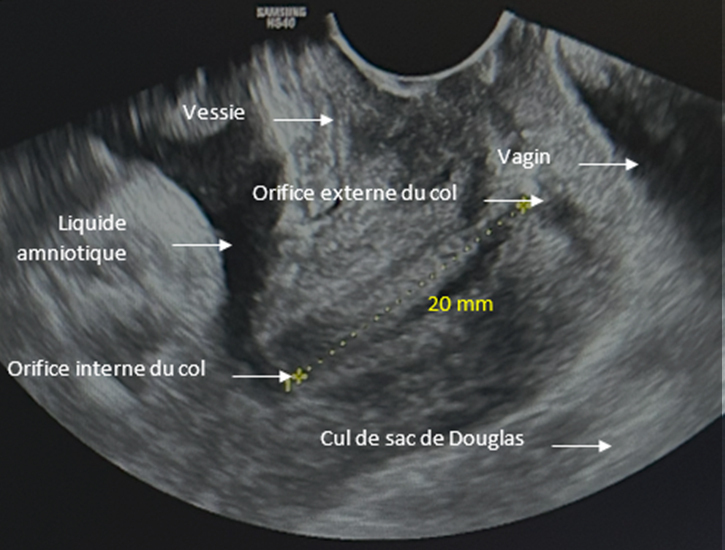

Voici le résultat de la cardiotocométrie et de l’échographie du col réalisée par voie endovaginale.

Figure 5 (Rodolphe Matias de Sousa, La Revue du Praticien)

Une menace d’accouchement prématuré se définit comme des contractions utérines régulières et douloureuses (ici 5 par dix minutes visibles à la tocométrie) et un col raccourci ou modifié cliniquement (ici mesuré à 20 mm à l’échographie endovaginale). Un col non modifié est dit long, tonique, postérieur, fermé avec une présentation fœtale non sollicitante.

Concernant l’échographie endovaginale.